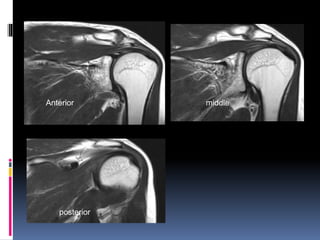

Anterior middle posterior

Coronal sections

Posterior sections of shoulder

Anterior middle

posterior